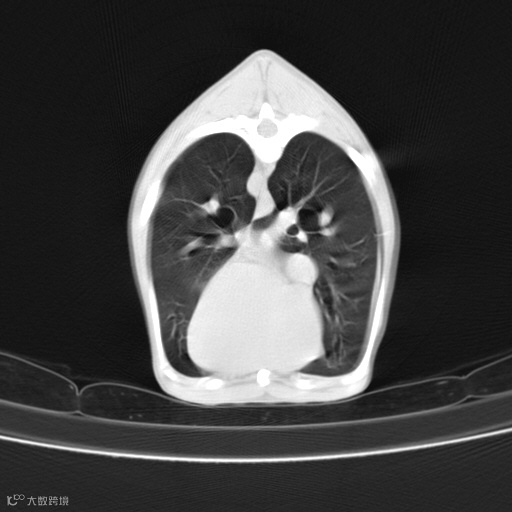

图像中能够显示的最小细节。观察图像中能否清晰识别小的解剖特征,并排除模糊或失真的情况。高分辨率图像可以清晰地显示小的解剖结构和病变。

肺部高分辨

图像中不同组织和结构之间的灰度差异。观察图像中相邻组织的灰度差异,并确保没有过度和欠度对比的情况。良好的对比度能够清晰地显示不同组织的边界和细节。

肝实质/肝内血管清晰